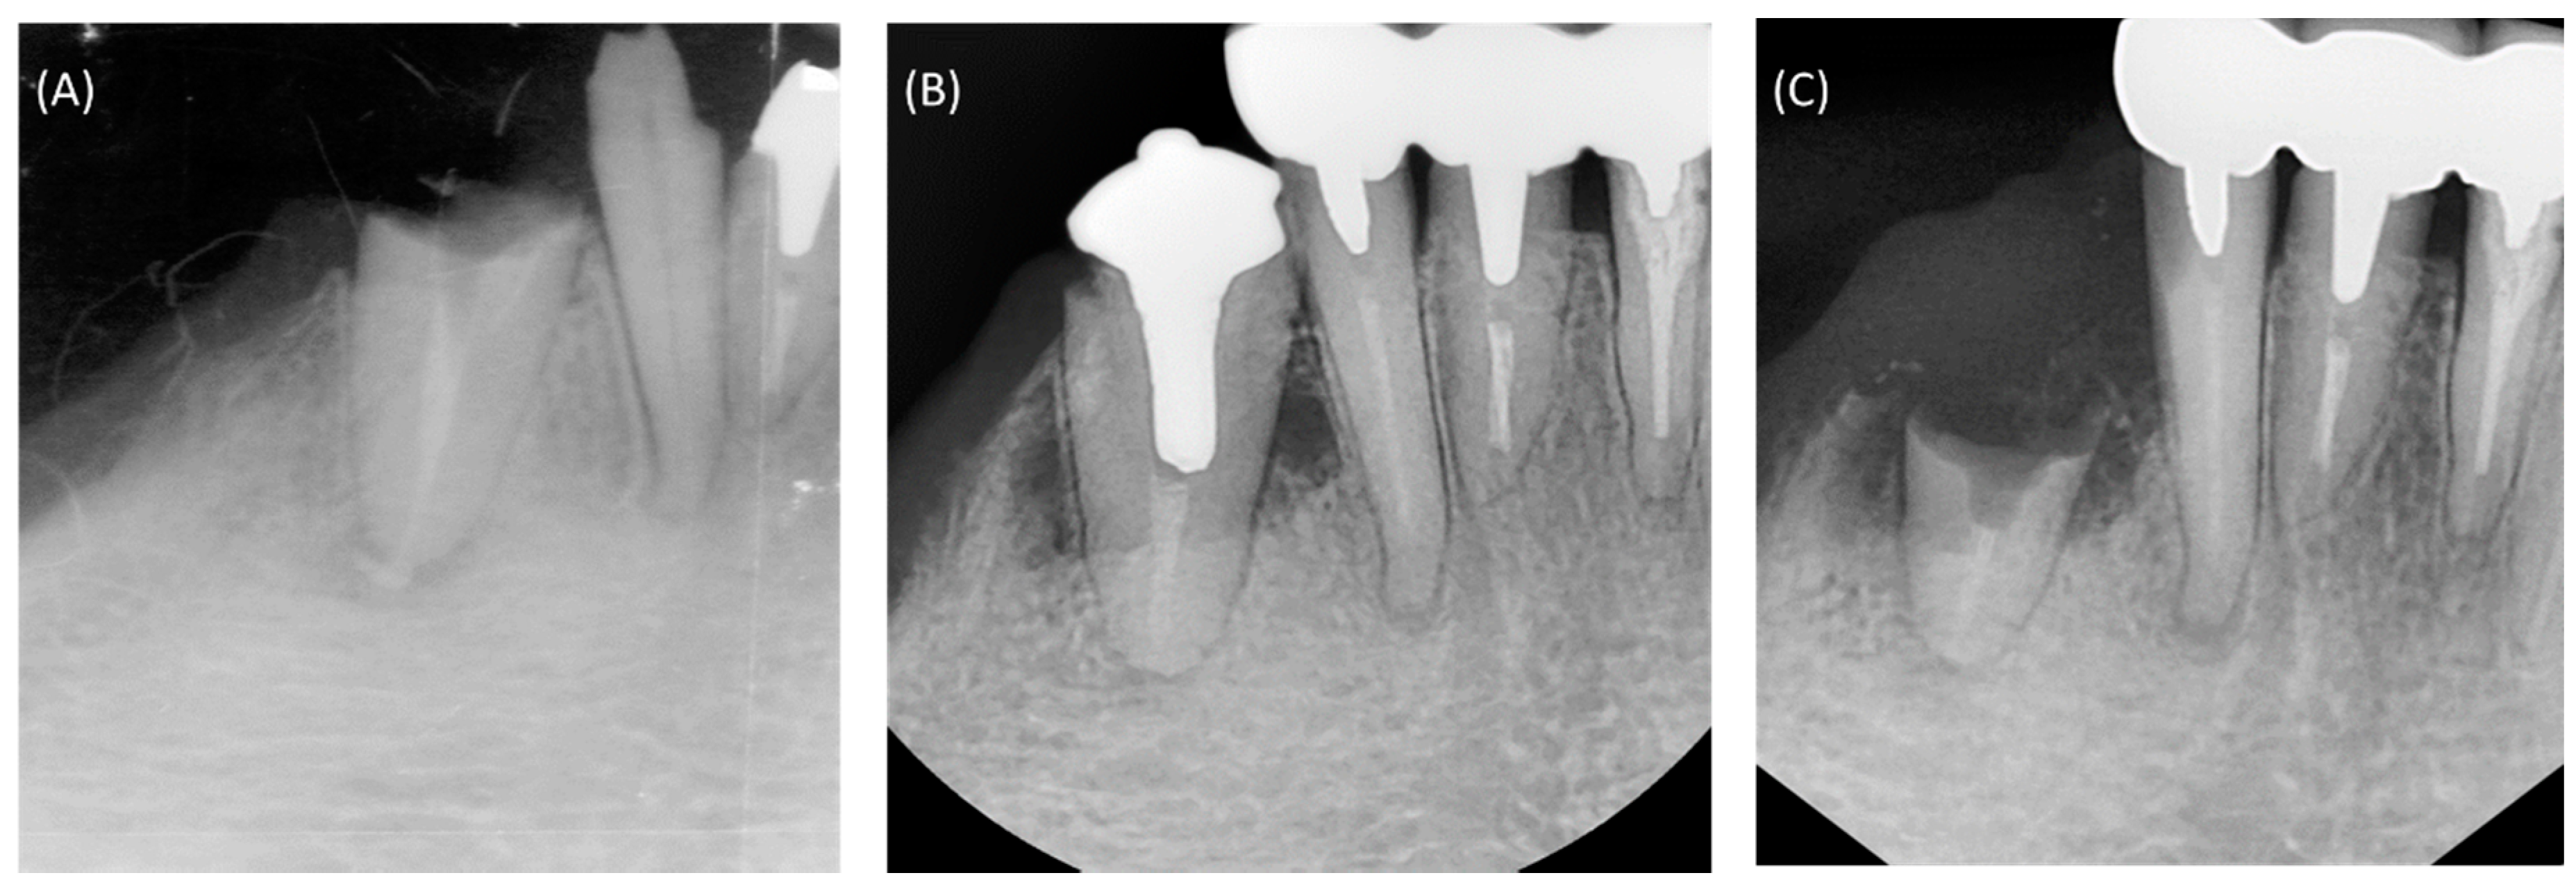

2. Clinical Presentation and Treatment